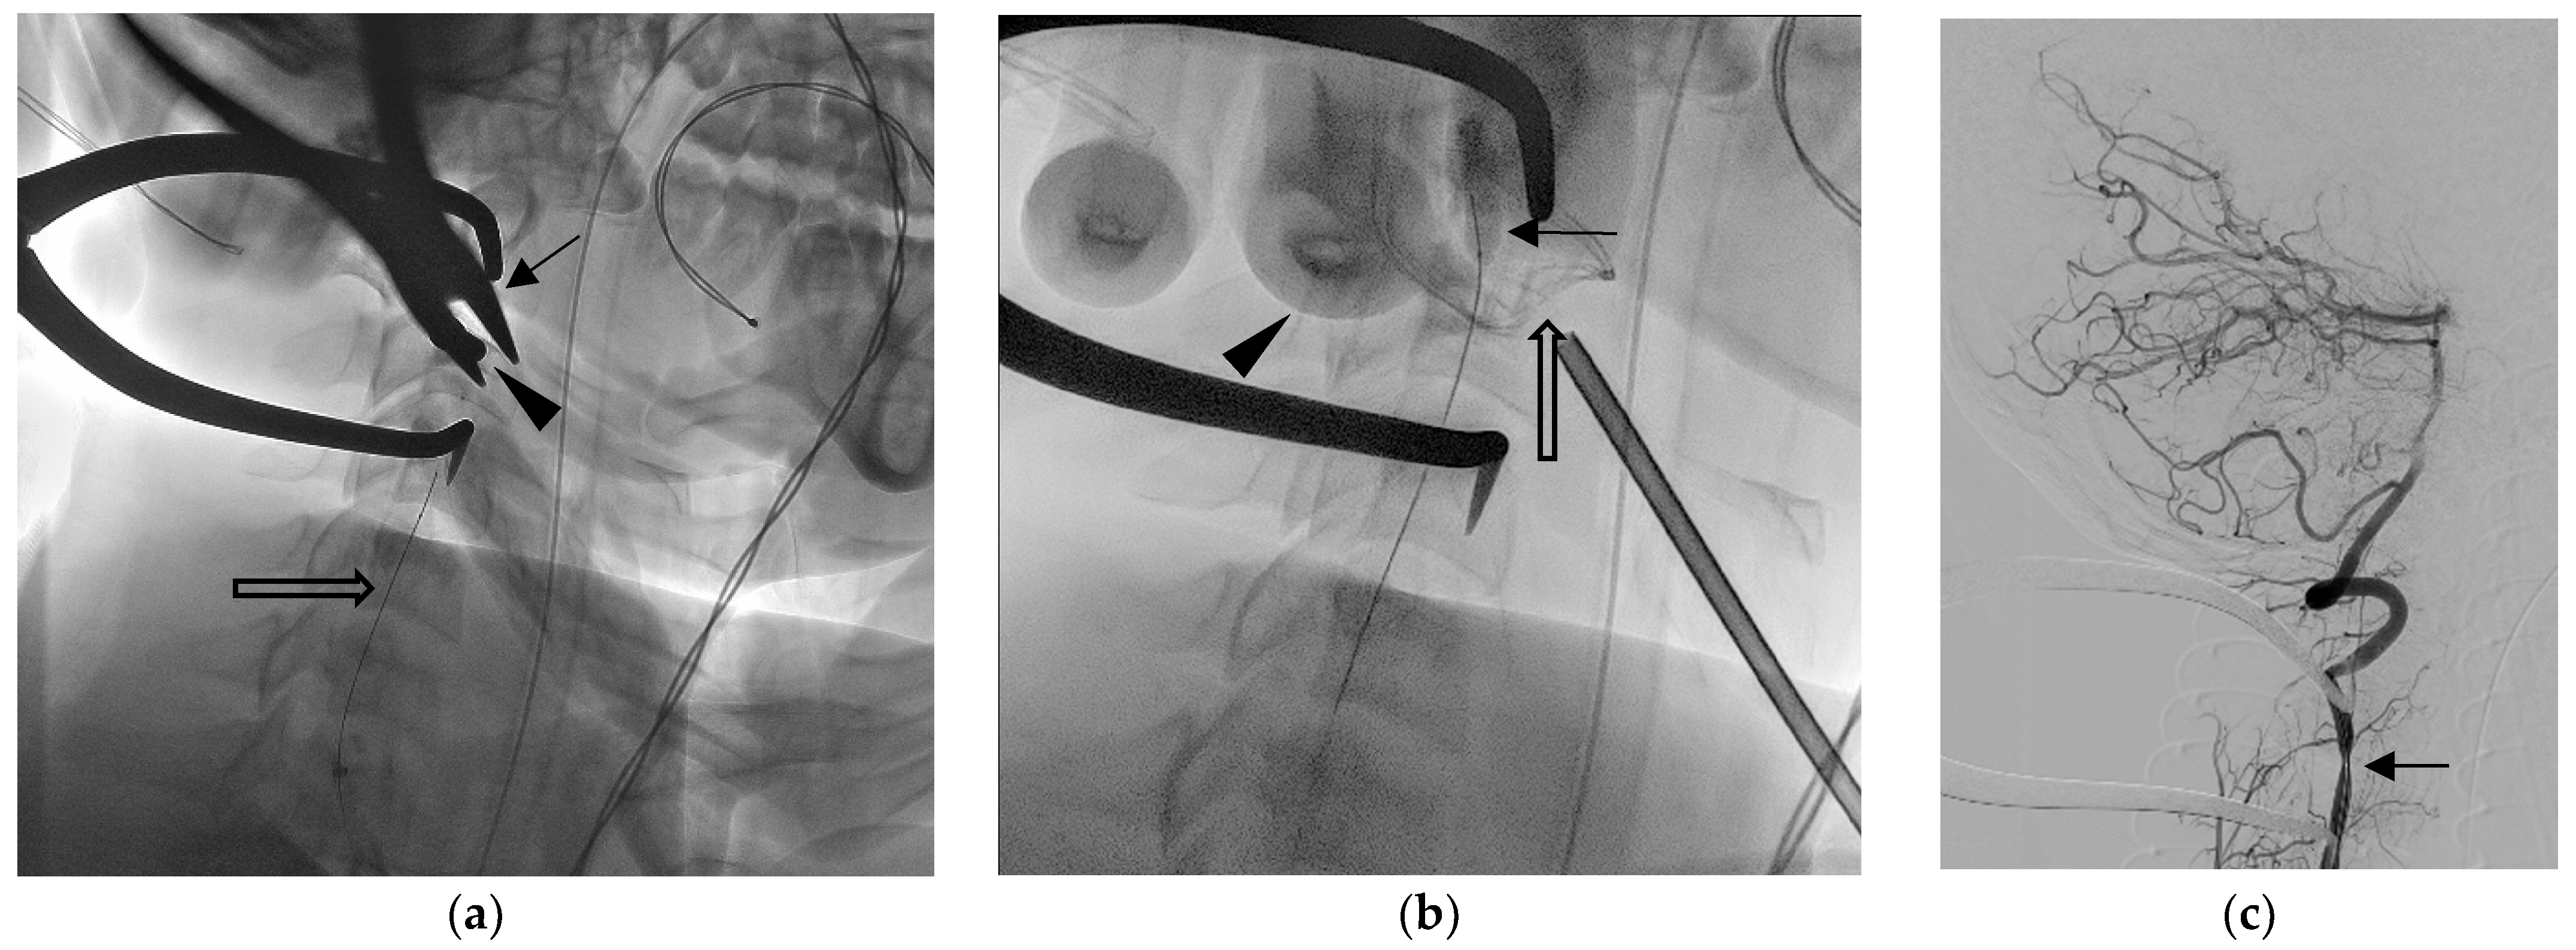

Figure 3.

Wound exploration was performed in hybrid operating suite [2]. Fluoroscope images showed the (a) surgical plier (arrow) grabbing the arrowhead (arrow), and the occlusion balloon catheter was deployed but not inflated (open arrow). After arrowhead extraction, oozing from the wound was noted. (b) The balloon was inflated (arrow) to decrease blood flow while the neurosurgeon applied direct compression (finger imaged, arrowhead) with gauze (open arrow) before performing a further hemostasis procedure. After that, the balloon was released. The following right vertebral angiography (c) shows focal narrowing of the artery lumen without extravasation. The patient reported no neurological deficit either when discharged or during their visit to the outpatient clinic 3 months later [3,4,5,6].